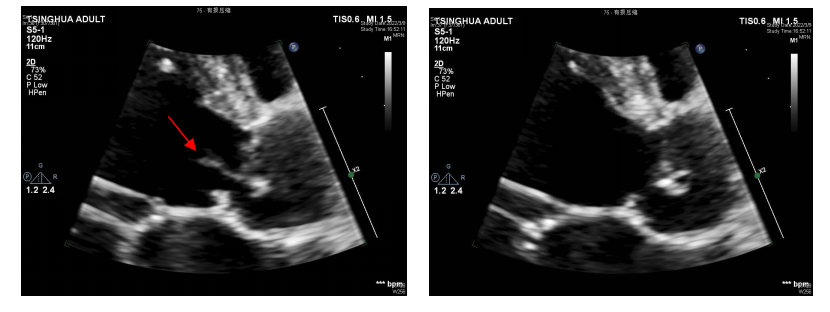

3)2周后,患者体力恢复良好,随即在全麻低温体外循环下行主动脉瓣机械瓣置换术。术中可见升主动脉及主动脉窦部正常,主动脉瓣左冠瓣及无冠瓣均有穿孔。同时,无冠瓣可见赘生物形成。(如图5-A,B)